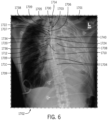

• FIGS. 6 and 7 are exemplary embodiments of combined images 1702 (e.g., DICOM image) such as that produced by the method 1600 in block 1612 identifying a catheter, tube or line 1705 within a patient that may be displayed on a display or other output device 1324.

• the combined images 1702 are chest images 1701 of a patient showing an CVC 1705 disposed within the central vein and including an overlay 1703.

• the overlay 1703 includes a first graphical marker 1734 (e.g., circle) overlaid on the chest image 1701 indicates the location of the tip or end 1707 of the CVC 1705.

• a second graphical marker 1736 (e.g., solid circle with chevron) overlaid on the chest image indicates a desired placement location 1737 for the tip 1707, which can be determined relative to or the same as a reference or anatomical landmark location 1709 (e.g., vertebrae 1704, carina 1712, trachea 1714, which can be the same or different for each anatomical location 1709).

• a third graphical marker 1738 indicates a distance 1720 (e.g., Euclidian distance) between the end 1707 of the CVC 1705 and the second graphical marker 1736.

• a numerical value 1740 for the measured distance accompanies the graphical marker 1738.

• the patient coordinate system 1700 including the vertical axis 1706, the horizontal axis 1708, and the horizontal component 1722 and vertical component 1724 of the distance 1720 as determined relative to the patient coordinate system 1700 and accompanied by their independent numerical values 1740.